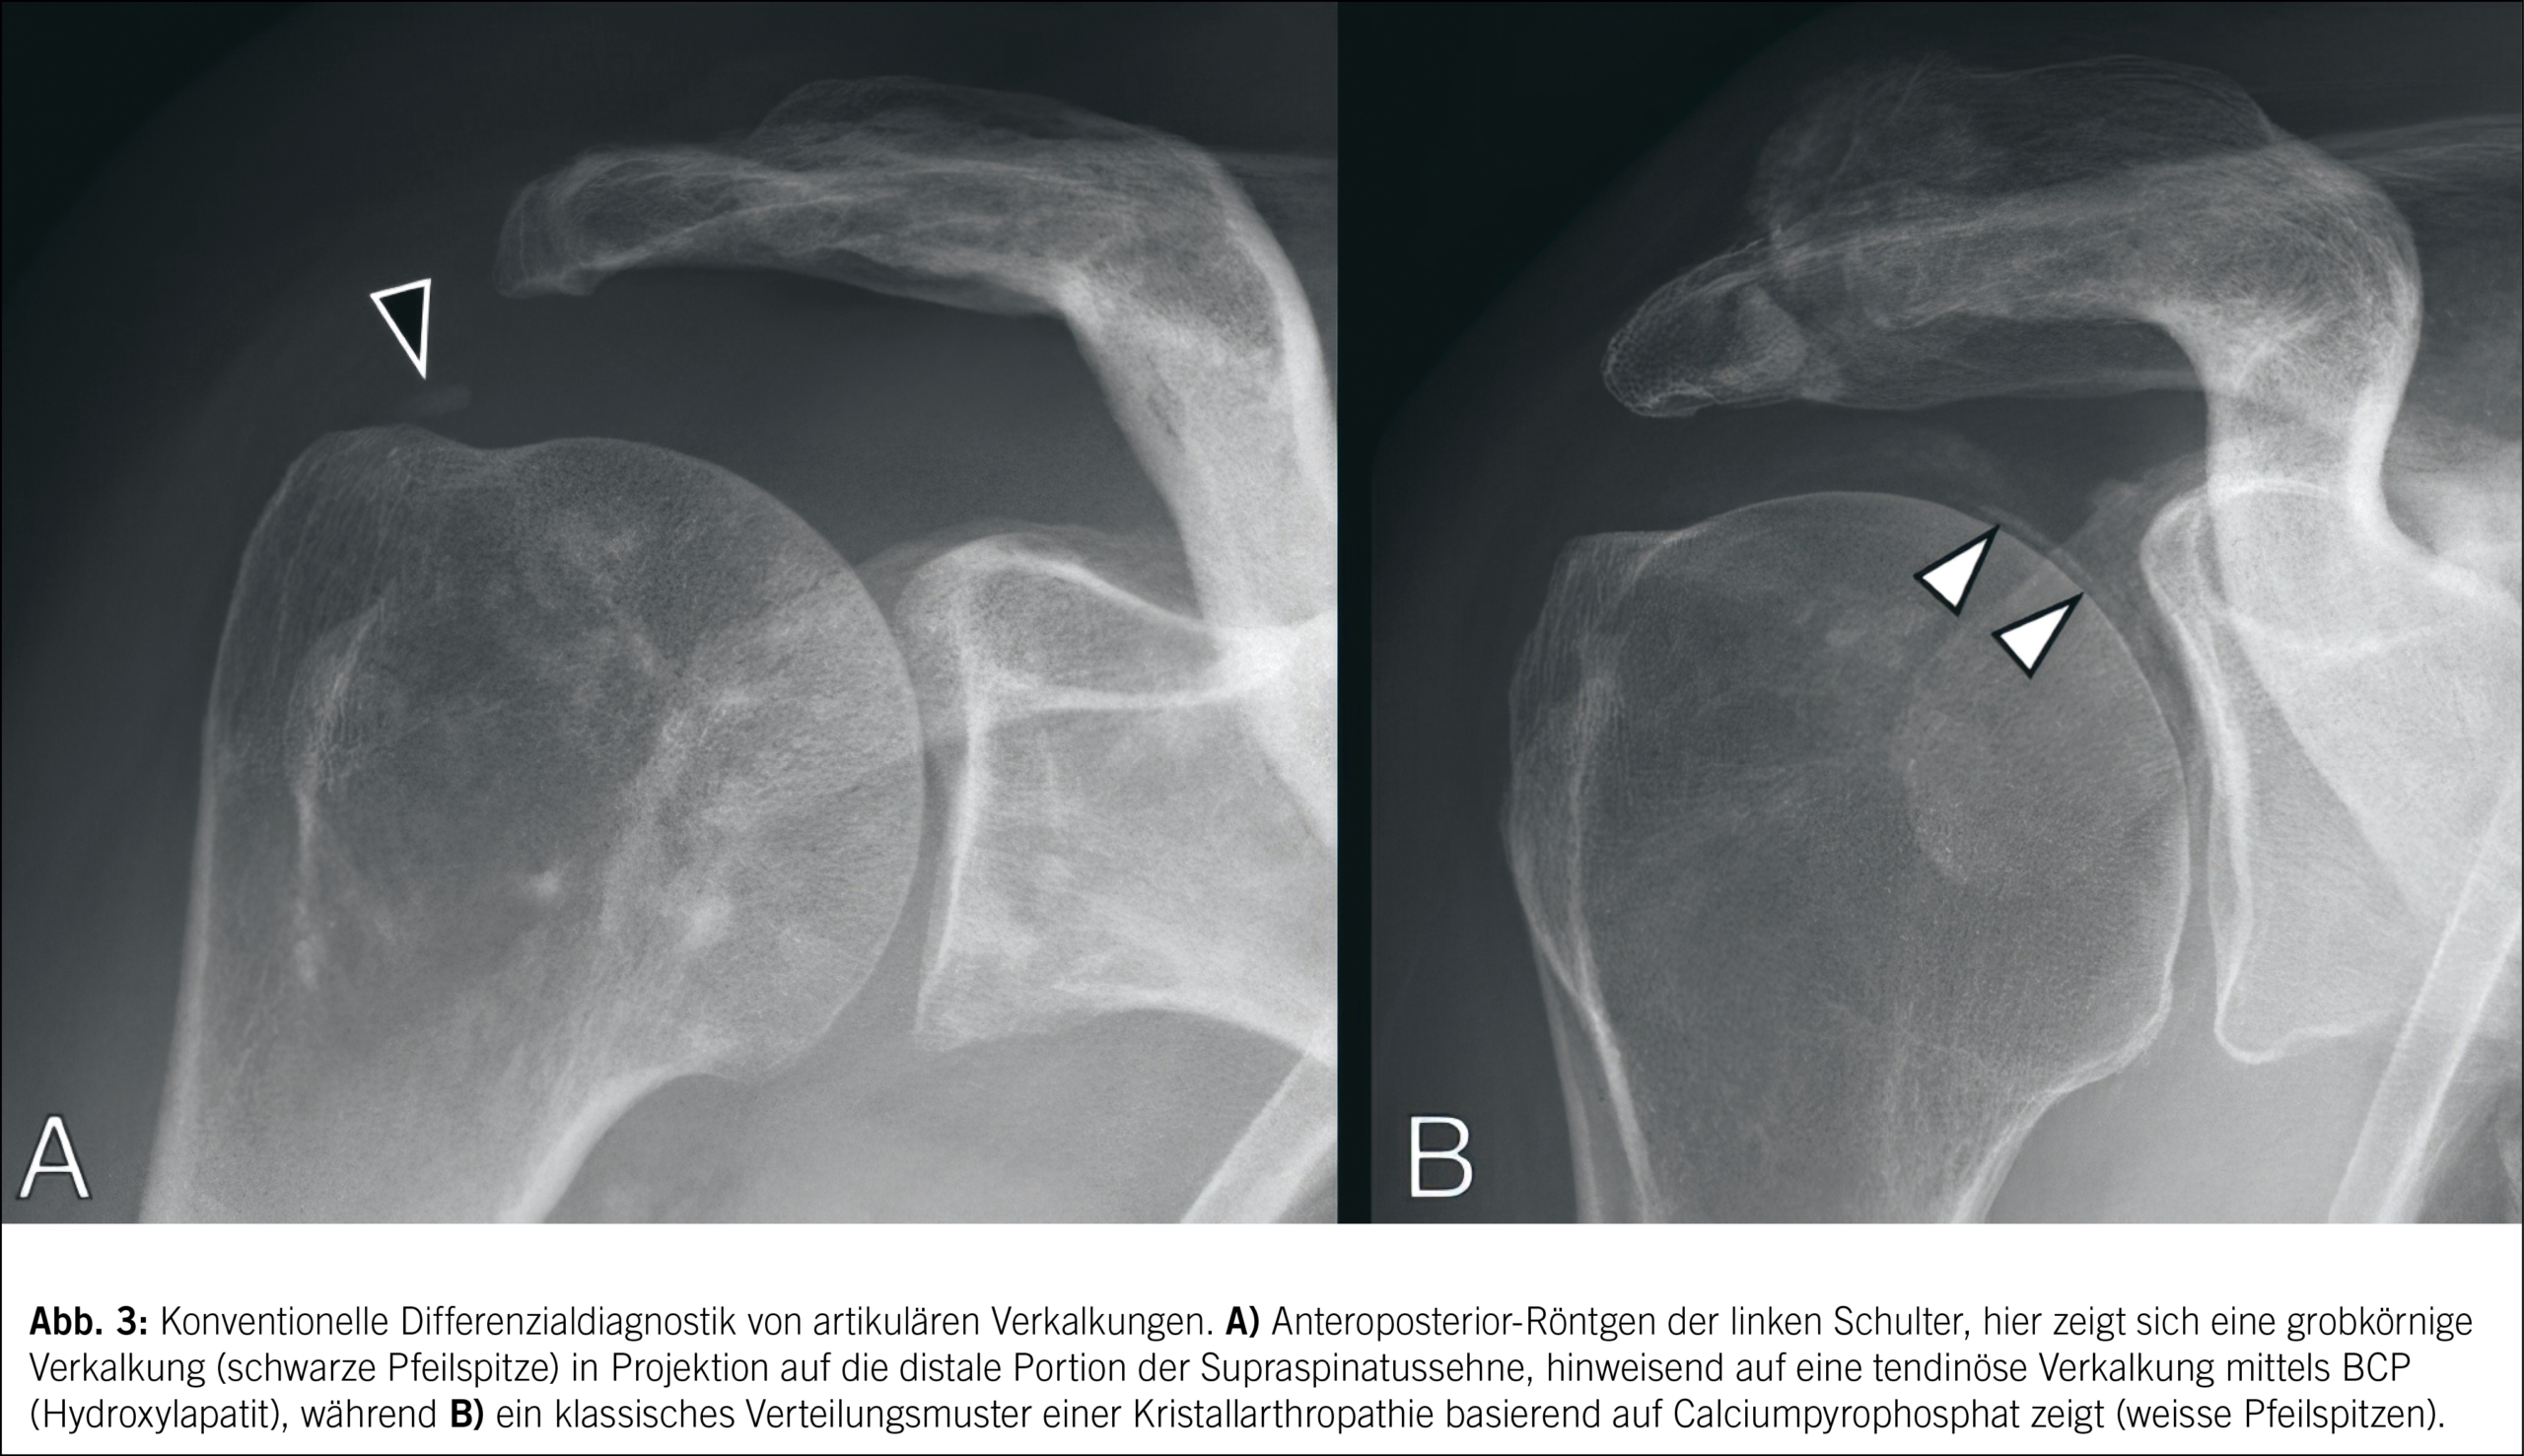

BCPD

Bei der Deposition von Basiskalziumphosphaten (BCP), wie z. B. Calciumhydroxyapatit, handelt es sich um eine weitere spezifische Form von Kristallarthropathien. Die BCPD wird erstmals meist mittels Röntgen diagnostiziert, wobei Verkalkungen in den Weichteilen, insbesondere um die Gelenke, sichtbar gemacht machen. Ein besonders häufiger Befund sind dichte, amorphe Verkalkungen um Sehnen und Bänder. Bei der Tendinitis calcarea, einer häufigen Manifestation der BCPD, manifestieren sich Depositionen am häufigsten im Bereich der distalen Supraspinatussehne. Der Ultraschall bietet eine hohe Sensitivität bei der Detektion von BCPD-Verkalkungen. Diese zeichnen sich durch echogene, dichte Strukturen mit posteriorer Schallauslöschung aus (Abb. 3). Diese Methode ist besonders nützlich für die Beurteilung der Schulter, wo die BCPD am häufigsten in der Rotatorenmanschette auftritt. In der MRT können BCP-Verkalkungen indirekt durch Signalintensitätsveränderungen und umgebende Entzündungsreaktionen identifiziert werden. Hierbei ist eine niedrige Signalintensität der Verkalkungen in T1- und T2-gewichteten Sequenzen typisch. Dies ist besonders hilfreich bei der Beurteilung von BCPD im Zusammenhang mit Sehnenschäden und Enthesiopathien.